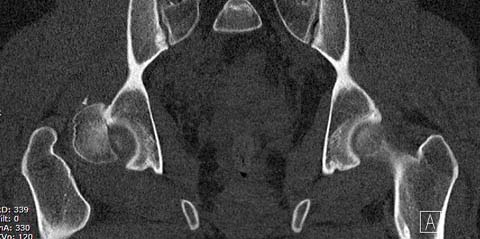

Здесь клинические примеры: Первый случай передний доступ, второй с ICP

monitor Flipp Trochanteris

и с переломом заднего края.